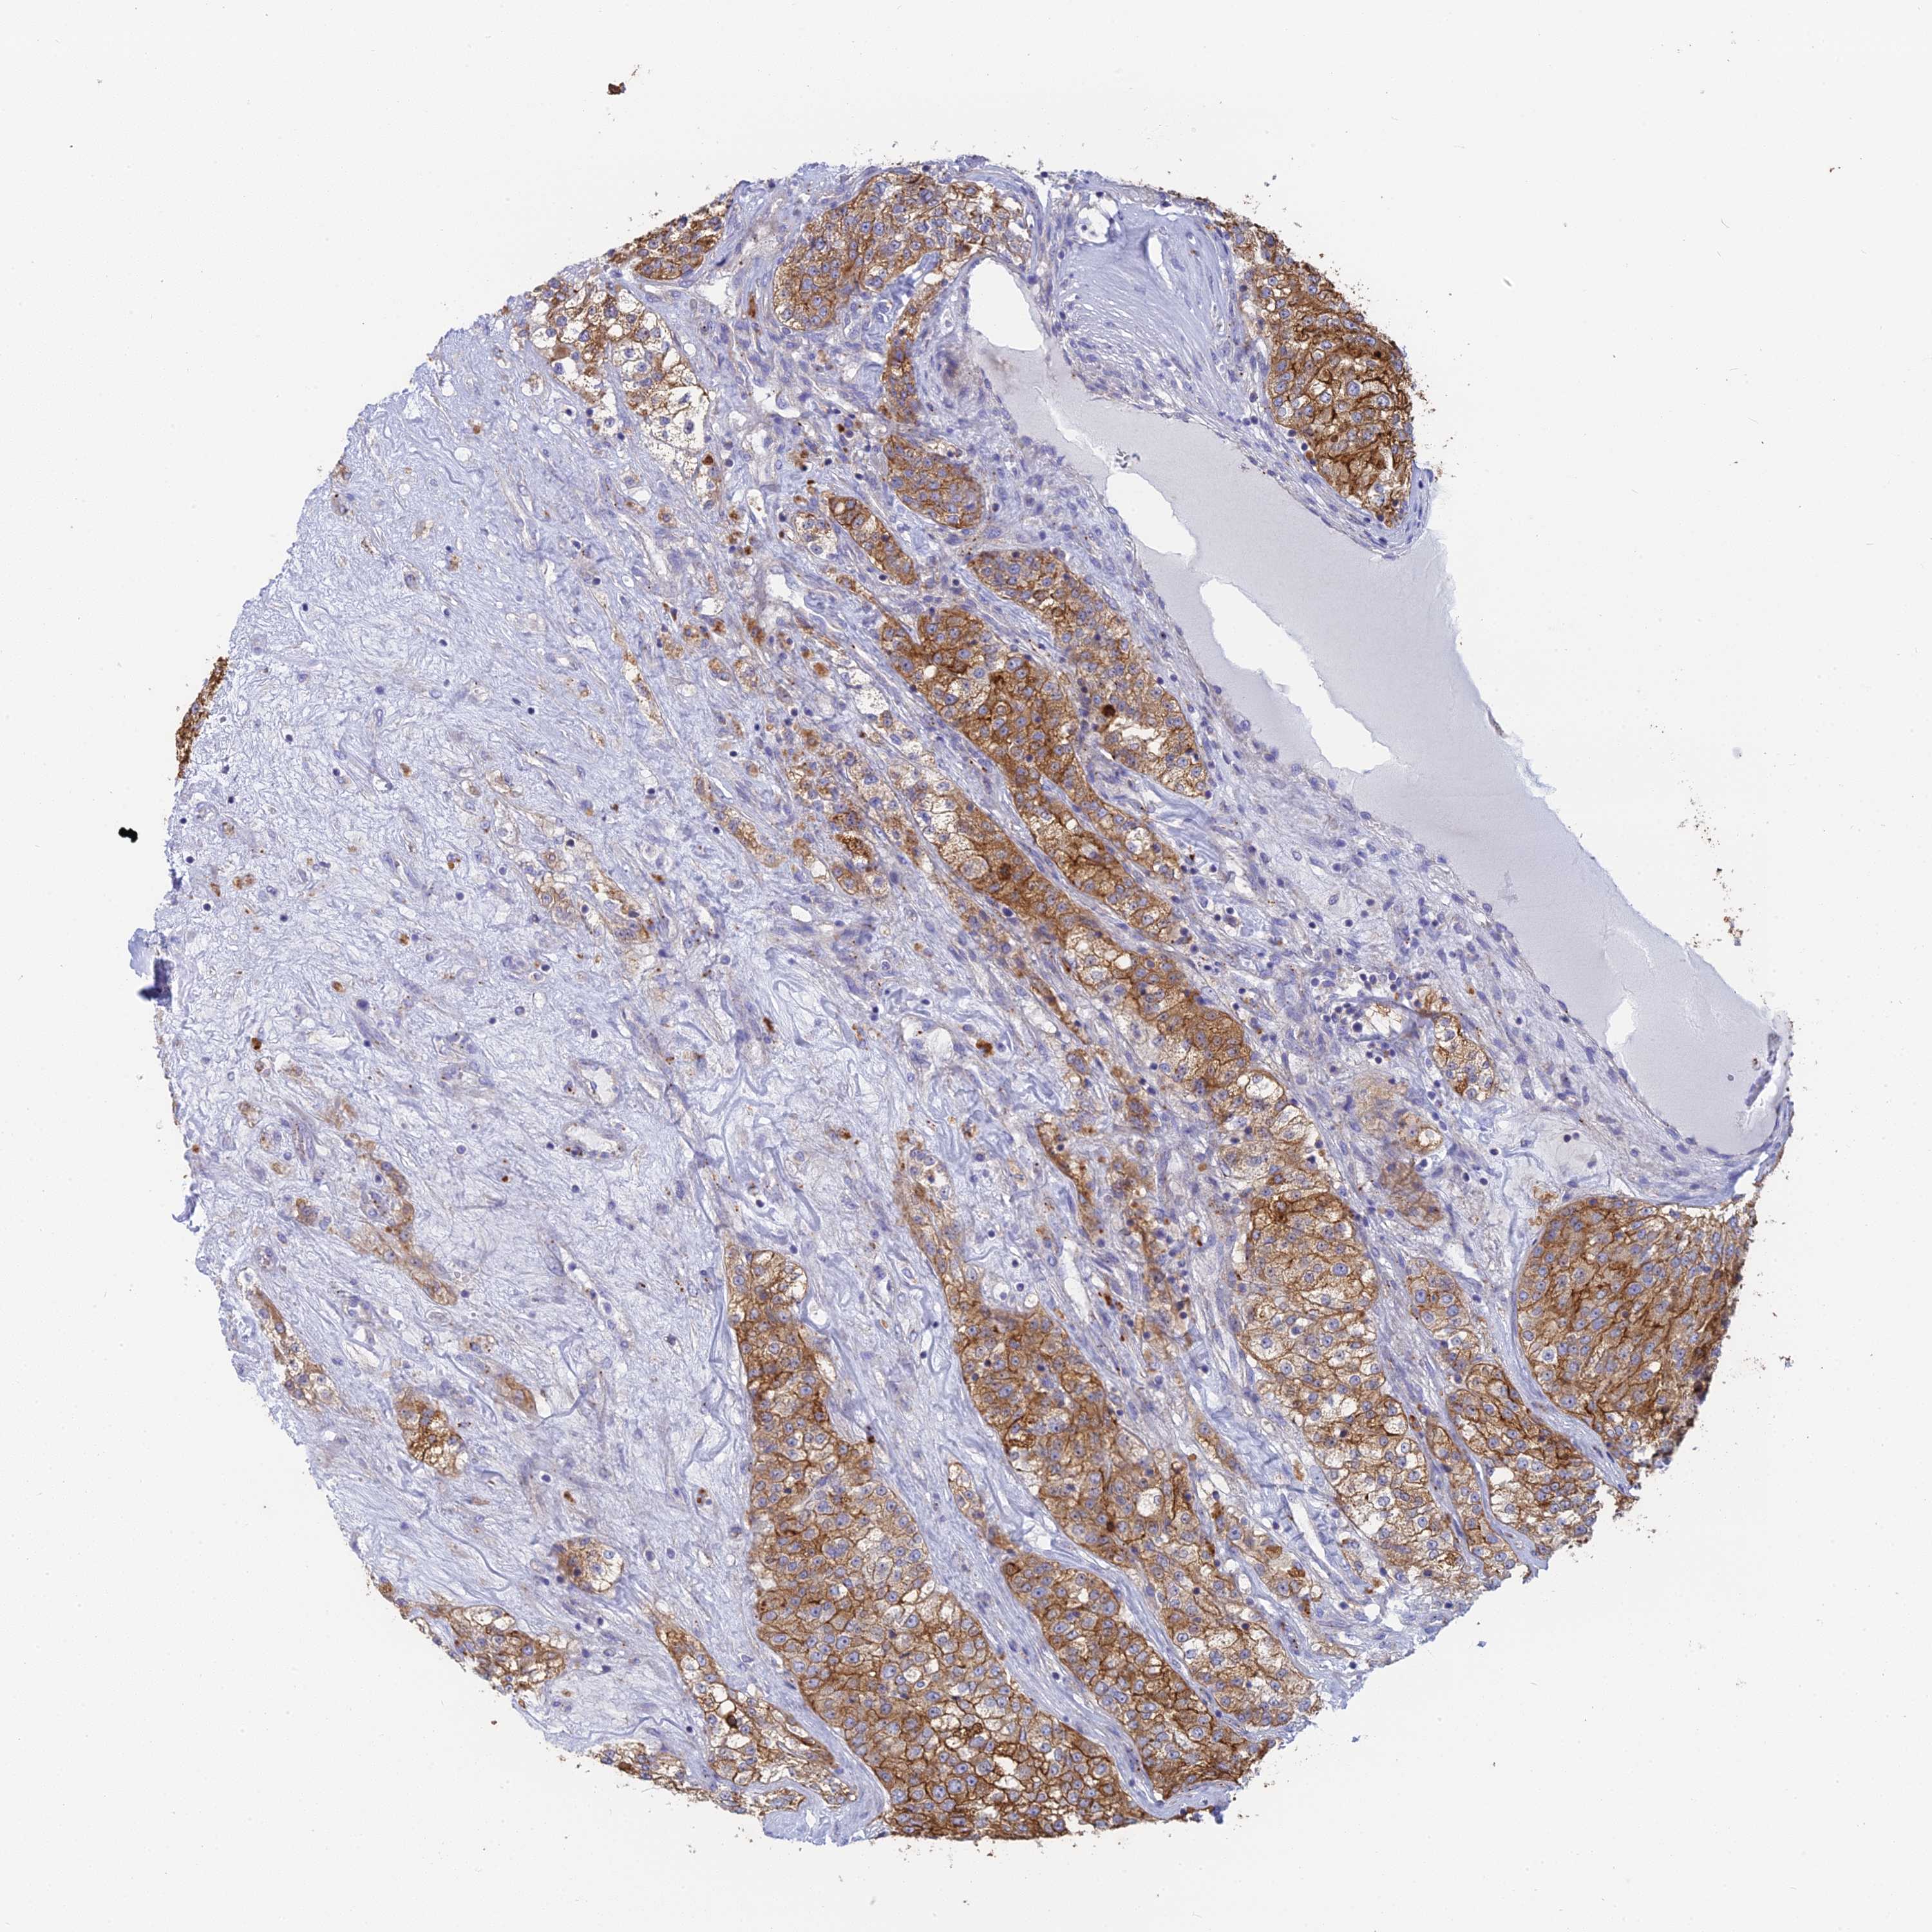

KIDNEY RENAL CLEAR CELL CARCINOMA (VALIDATION) - Interactive survival scatter ploti

The Survival Scatter plot shows the clinical status (i.e. dead or alive) for all individuals in the patient cohort, based on the same data that underlies the corresponding Kaplan-Meier plots. Patients that are alive at last time for follow-up are shown in blue and patients who have died during the study are shown in red.

The x-axis shows the expression levels (FPKM) of the investigated gene in the tumor tissue at the time of diagnosis. The y-axis shows the follow-up time after diagnosis (years). Both axes are complimented with kernel density curves demonstrating the data density over the axes. The top density plot shows the expression levels (FPKM) distribution among dead (red) and alive patients (blue). The right density plot shows the data density of the survived years of dead patients with high and low expression levels respectively, stratified using the cutoff indicated by the vertical dashed line through the Survival Scatter plot. This cutoff is automatically defined based on the FPKM cutoff that minimizes the p-score. The cutoff can be changed by dragging the vertical line or by entering a cutoff value in the square labeled "Current cut-off".

Under the Survival Scatter plot the p-score landscape (black curve; left axis) is shown together with dead median separation (red curve; right axis). Dead median separation is the difference in median mRNA expression between patients who have died with high and low expression, respectively. It is calculated as follows: median FPKM expression of dead patients with high expression - median FPKM expression of dead patients with low expression. This is intended to aid the user in visually exploring custom cutoffs and the associated p-scores and dead median separation.

Individual patient data is displayed and can be filtered by clicking on one or more of the category buttons on the top of the page. Categories describing expression level and patient information include: high, low, alive, dead, female, male and tumor stages. The scale of the x-axis can be toggled between linear and log-scale by clicking on the "x log" button. Mouse-over function shows TCGA ID, patient information and mRNA expression (FPKM) for each patient.

& Survival analysisi

Kaplan-Meier plots summarize results from analysis of correlation between mRNA expression level and patient survival. Patients were divided based on level of expression into one of the two groups "low" (under cut off) or "high" (over cut off). X-axis shows time for survival (years) and y-axis shows the probability of survival, where 1.0 corresponds to 100 percent.

WDR6 is not prognostic in Kidney Renal Clear Cell Carcinoma (validation)

: 51.97

Average pTPM 51.1

Number of samples 100